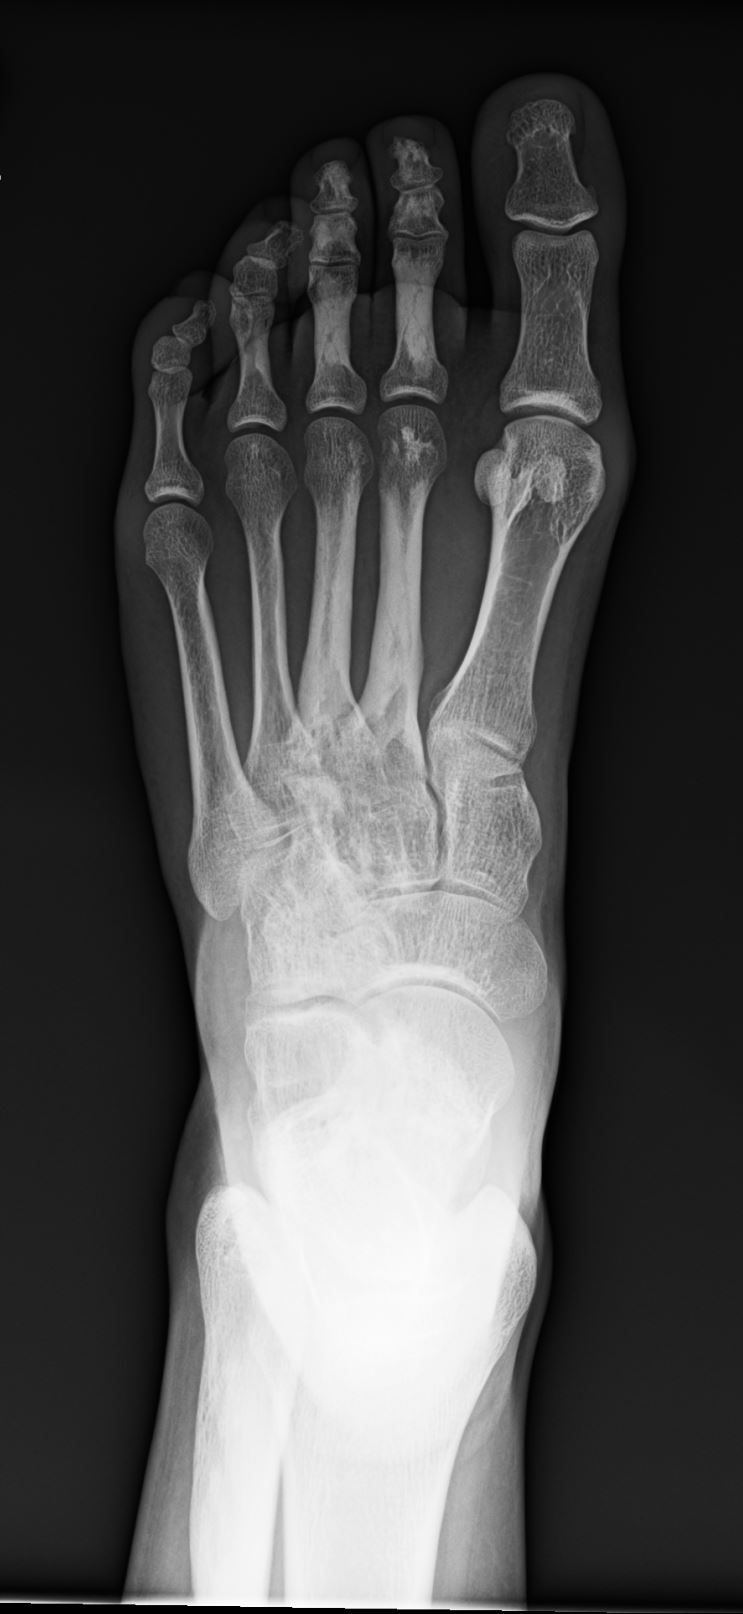

20-year-old female with chronic dorsal foot pain. What most likely represents the imaging finding?

What is your diagnosis?